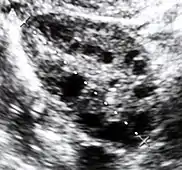

| Diagnostic method | Blood tests, ultrasound[1][4] |

Polycystic ovary syndrome accounts for about 70% of hyperandrogenism cases.[1] Other causes include adrenal hyperplasia, insulin resistance, hyperprolactinemia, Cushing's disease, certain types of cancers, and certain medications.[4][1][3] Diagnosis often involves blood tests for testosterone, 17-hydroxyprogesterone, and prolactin, as well as a pelvic ultrasound.[1][4]

Polycystic ovary syndrome (PCOS) is an endocrine disorder characterized by an excess of androgens produced by the ovaries. It is estimated that approximately 90% of women with PCOS demonstrate hypersecretion of these hormones.[18] The cause of this condition is unknown. Speculations include genetic predisposition; however, the gene or genes responsible for this remain unidentified.[19] The condition may have a hereditary basis. Other possible causes include elevated insulin production. Most cases of PCOS involve insulin resistance.[20] It is thought that adipose tissue dysfunction plays a role in the insulin resistance seen in PCOS.[20] Insulin can induce excess testosterone secretion from the ovaries.[21] A complication associated with polycystic ovary syndrome is high cholesterol, which is treated with statins. In a meta-analysis, atorvastatin was shown to decrease androgen concentrations in people with hyperandrogenism.[22]